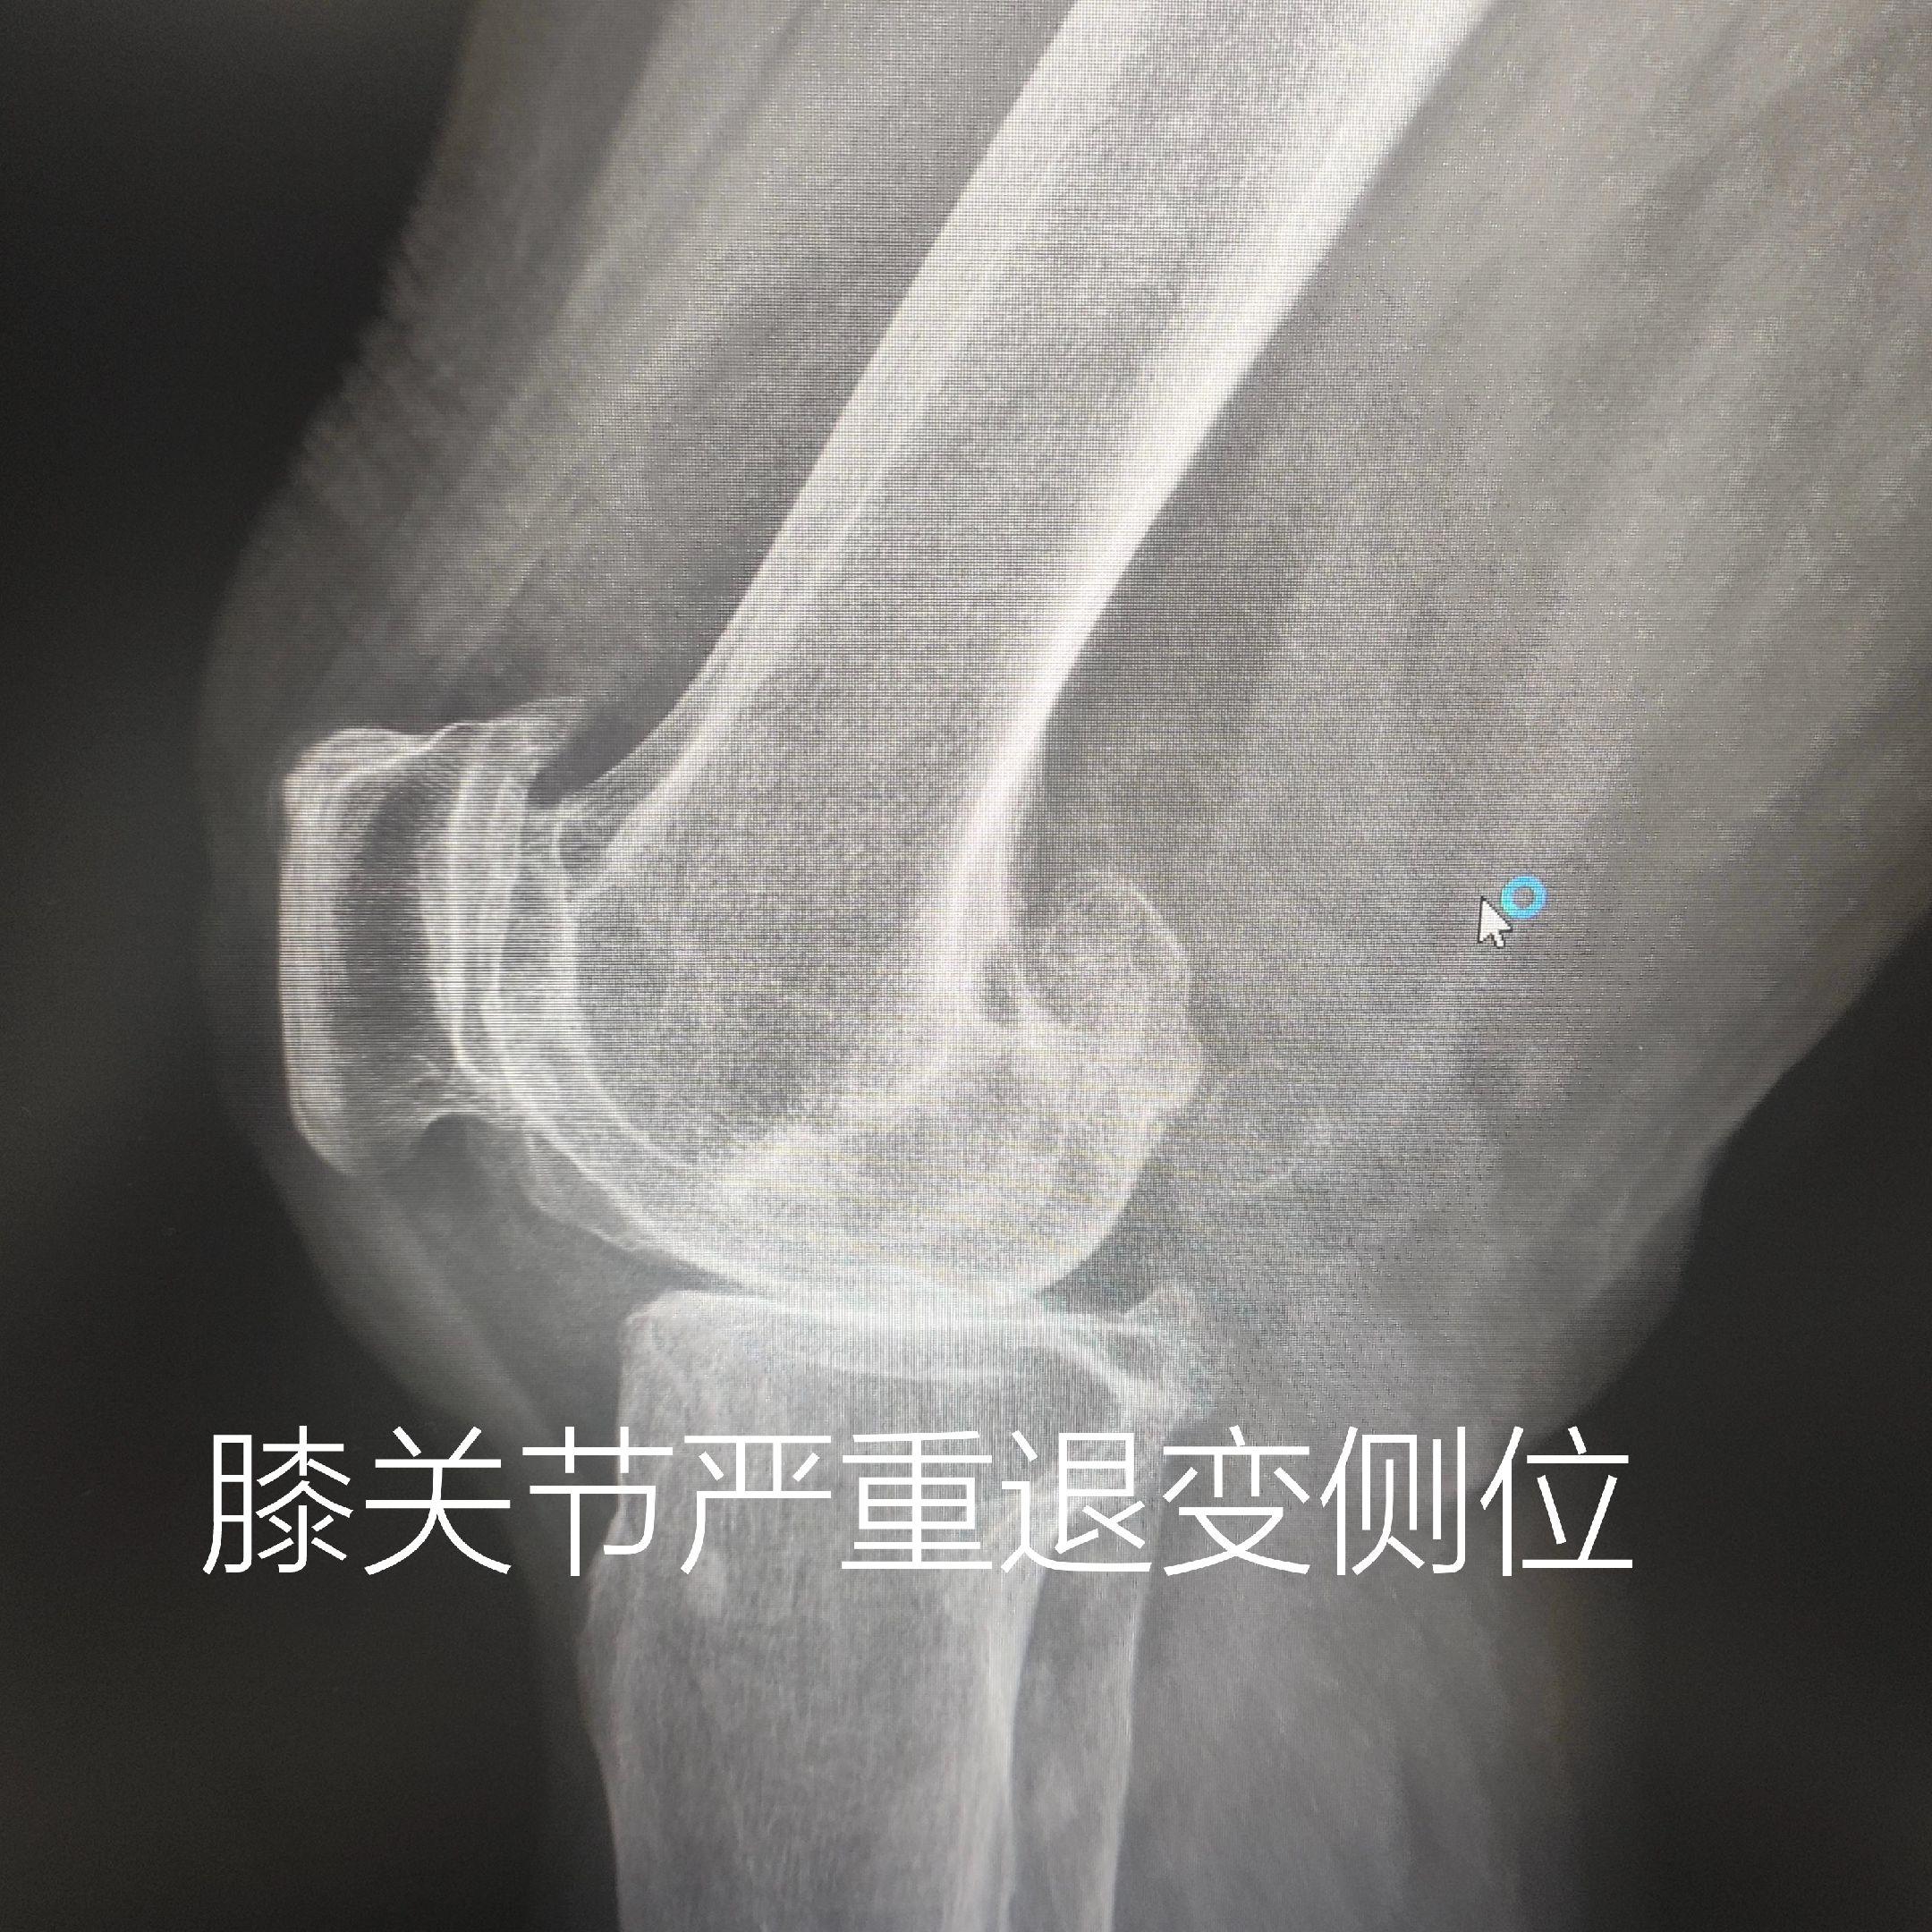

膝关节痛。